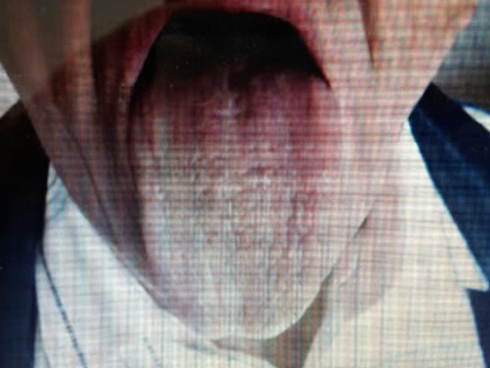

58 year old man with slurring of speech and progressive difficulty in swallowing

O/E

Weak jaw and facial muscles, limb weakness with both lower and upper motor neuron signs and tongue muscle atrophy.

What investigation is recommended?

Electromyography (EMG) and nerve conduction studies, genetic testing for specific motor neuron diseases -

What is the most likely diagnosis?

Amyotrophic Lateral Sclerosis (ALS) or Motor Neuron Disease